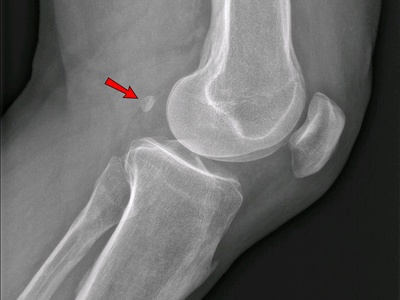

Fabella

The fabella is a small sesamoid in the lateral gastrocnemius tendon behind the knee. It’s variable across populations and may influence knee mechanics. When symptomatic it causes posterolateral knee pain, can impinge after knee replacement, or be mistaken for loose bodies.

Cyamella (popliteus sesamoid)

The cyamella is a very rare sesamoid found in the popliteus tendon near the posterior knee. It’s usually an incidental imaging finding but can occasionally cause posterolateral knee pain or confusing radiographs. Reports in humans are uncommon.